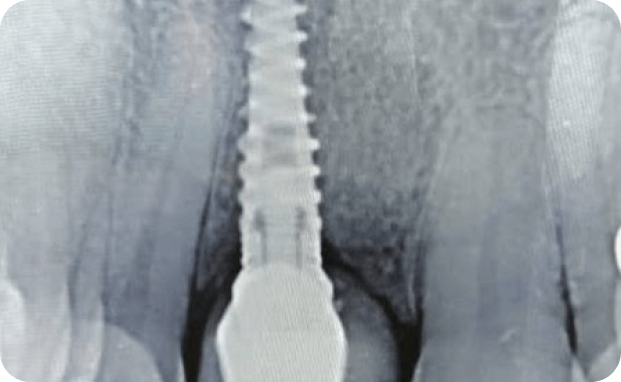

Casos